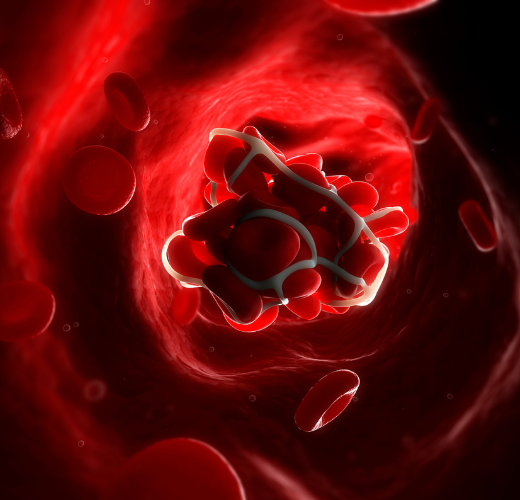

Laresistencia a la insulina es la causa de la enfermedad. En esta enfermedad, las células del organismo ya no son capaces de utilizar la insulina, la hormona que controla la utilización del azúcar. En esta situación, la concentración de glucosa en la sangre aumenta considerablemente. Sin embargo, la glucosa en sangre no es el único factor que se altera. De hecho, las investigaciones han descubierto en quienes padecen esta enfermedad niveles de vitamina A y C más bajos de lo normal. Y no sólo eso: los enfermos de esta forma de diabetes también se caracterizan por una menor actividad de la enzima paraoxonasa. Esta molécula circula en la sangre asociada al llamado colesterol "bueno " y tiene una importante función para contrarrestar las alteraciones del colesterol "malo " que favorecen laaterosclerosis.

Omega-3 que favorece la paraoxonasa contra la aterosclerosis

Científicos iraníes estudiaron los efectos del Omega-3 tomado en forma de complementos alimenticios sobre la actividad de la paraoxonasa y los niveles de vitamina A, C y E. En la investigación participaron 80 pacientes con diabetes de tipo 2, a los que se recetó Omega-3 (un total de 2,714 gramos al día) o un placebo durante 8 semanas. Al principio y al final del periodo de tratamiento, los investigadores extrajeron 10 mililitros de sangre de cada paciente (en ayunas). En las muestras, midieron los niveles de las 3 vitaminas, así como actividad paraoxonasa. Todos los pacientes rellenaron también un cuestionario sobre sus hábitos alimentarios los dos días anteriores y previos al tratamiento. cuestionario sobre sus hábitos alimentarios. El análisis estadístico de los datos recogidos mostró que la ingesta de Omega-3 aumentaba la actividad de la enzima en aproximadamente un 42%. En cambio, no se detectó ningún efecto de estos nutrientes sobre las concentraciones de vitamina A, C o E.